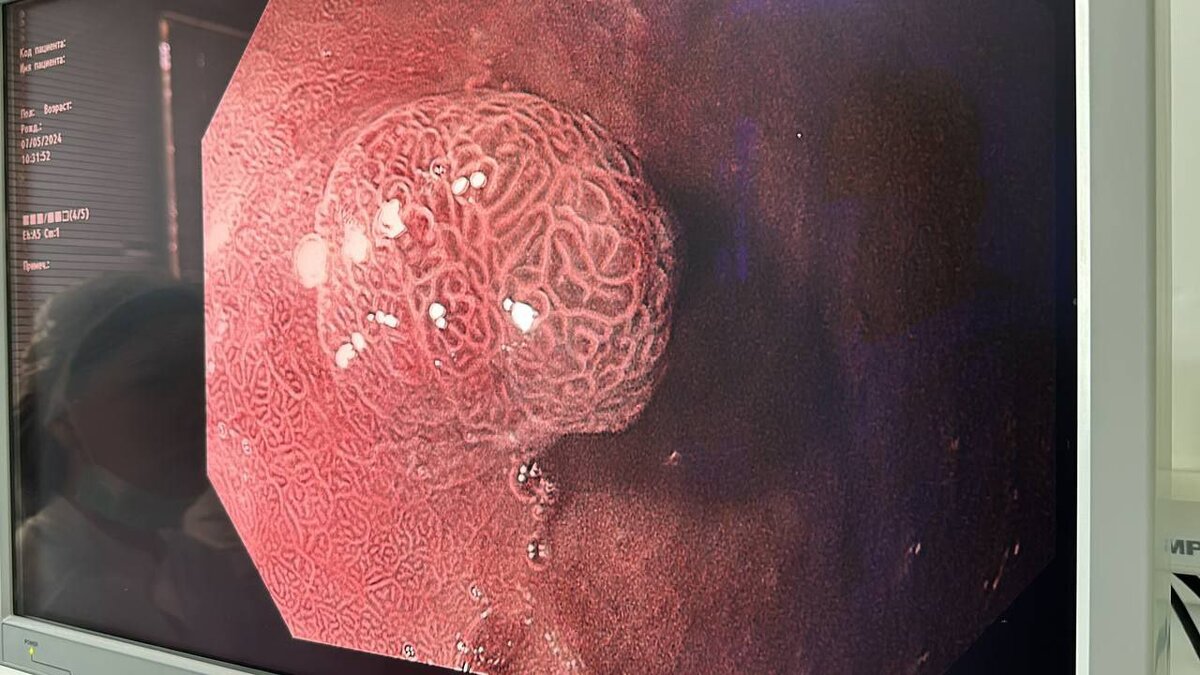

Видеоколоноскоп и гастроинтестинальный видеоскоп приобрели за 10 миллионов рублей, которые выделили из госбюджета.

Благодаря 60-кратному увеличению аппаратов специалисты могут рассмотреть кровеносные сосуды и слизистую во всех подробностях и выявлять патологии.

«За последние два года в рамках нацпроекта наше отделение полностью переоснастили современным оборудованием. Возможности аппаратов позволяют уже в ходе исследования предположить морфологическое заключение: данные о наличии или отсутствии злокачественных клеток. Проводим диагностику предраковых состояний, широко применяем оборудование в терапевтических целях, внедряем новые безоперационные методики лечения рака различных локализаций», — рассказывает заведующий эндоскопическим отделением ОКОД, главный внештатный эндоскопист министерства здравоохранения Астраханской области Дмитрий Богомолов.